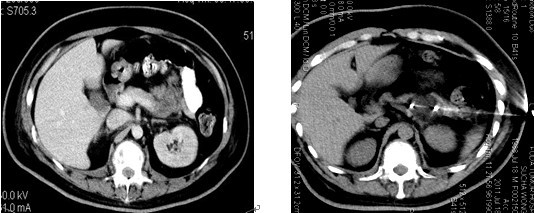

亮亮胰腺肿瘤治疗前CT片,显示胰腺体部大肿瘤 正在给亮亮的胰腺肿瘤作冷冻治疗